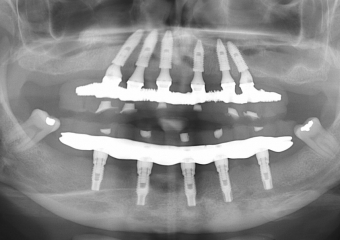

Raio X final